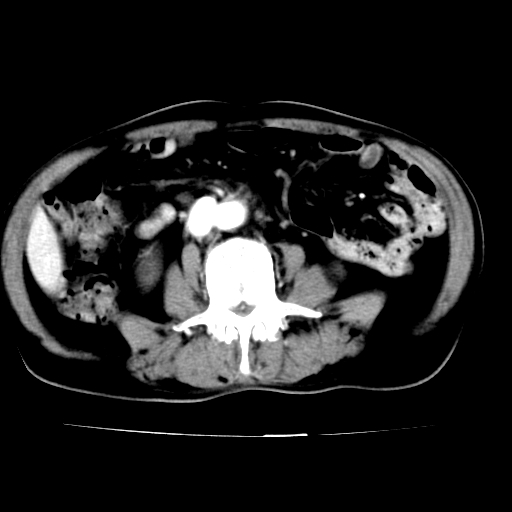

给平扫片看看血管壁钙化情况。

此病例平扫图像已发,请大家看看!